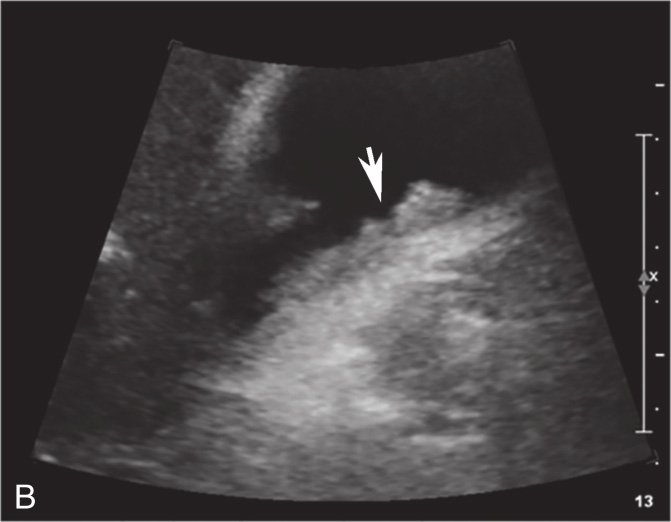

图2-5-1 结节型胆囊癌常规超声图像

A.胆囊壁可见高回声结节,最大径2.8cm;B.CDFI显示结节内可见血流信号